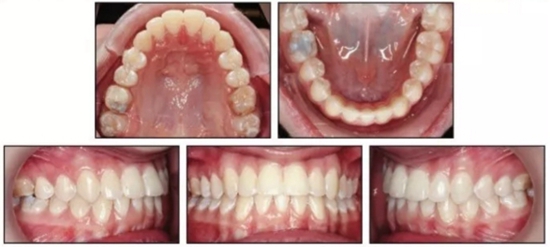

治療結(jié)束后,患者雙側(cè)達(dá)到安氏I類關(guān)系,正常的覆合覆蓋及接近理想的前牙軸傾度。頭側(cè)結(jié)果再次確認(rèn)了通過(guò)上頜伸長(zhǎng)安氏III已得到矯正,SNA從73.1°增大到78.1°(表1)。上頜前磨牙間寬度增加了約9mm。下頜MP-PP角減小了4.9°,面型接近中等面型。

患者繼續(xù)佩戴活動(dòng)保持器,治療后13月隨訪提示其仍處于一個(gè)穩(wěn)定的咬合關(guān)系。(圖5)